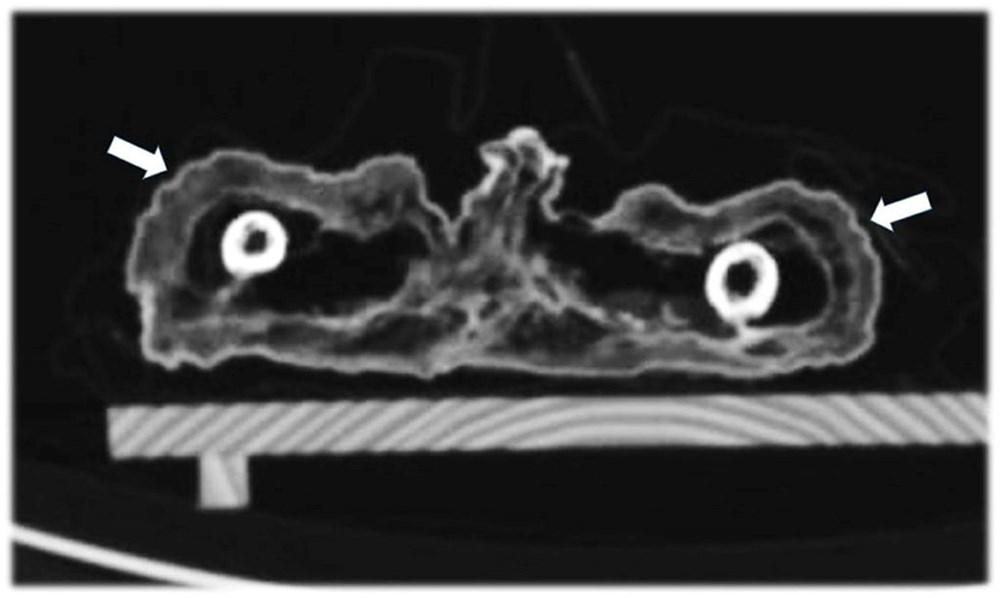

Araştırmacılar, vücudun kemiklerinin oluşumunu ve uzunluğunu ve ayrıca diş patlamasının kanıtlarını inceleyerek, çocuğun öldüğünde yaklaşık bir yaşında olduğunu tahmin edebildiler. Kemikler ayrıca, çocuğun iyi beslenmesine rağmen bozuk kaburgalarında raşitik tespih belirtileri bulundu. Bu durum, raşitizm (D vitamini) ve iskorbüt (C vitamini) gibi spesifik vitamin eksiklikleri ile ilişkili hastalıklardan kaynaklanır.

Münih-Bogenhausen Akademik Kliniği’nden ve baş araştırmacı Dr. Andreas Nerlich, “Şiddetli bir vitamin eksikliği ile obezitenin birleşimi, yalnızca genel olarak ‘iyi’ bir beslenme durumu ve neredeyse tamamen güneş ışığına maruz kalmama ile açıklanabilir” dedi.